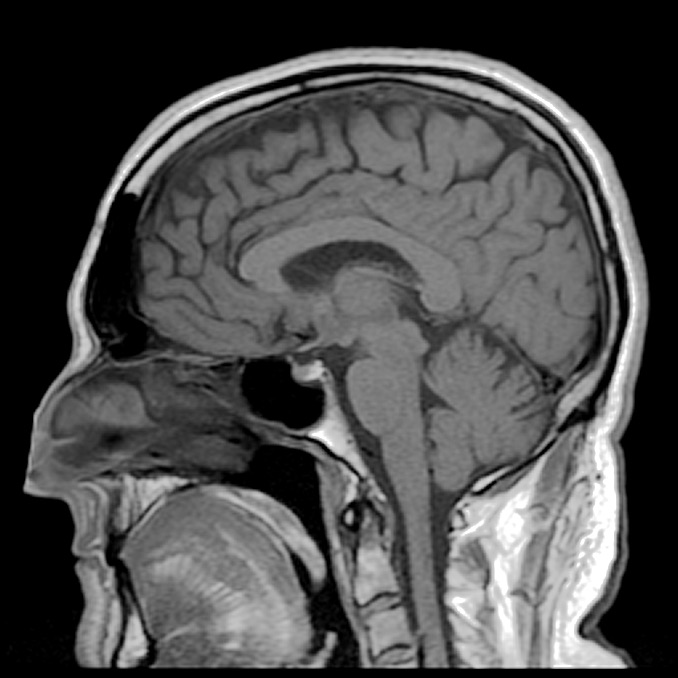

La doctora explica que el estudio que está llevando a cabo analiza imágenes por resonancia magnética del cerebro de una muestra de dos grupos diferenciadas de 19 varones cada una

En el primer grupo de individuos estos hombres están diagnosticados con comportamiento sexual compulsivo, que consumen cinco veces más de pornografía que el otro grupo y que muestran grandes dificultades para mantener su trabajo o sus relaciones íntimas mientras que el otro grupo, llamado “control”, estaba formado por varones sin comportamiento sexual impulsivo.

Durante la realizacion de este estudio se midieron los parámetros de respuesta cerebral mientras estas personas veian imágenes de sexo explícito.

Los resultados obtenidos muestran que los individuos con alguna alteracion relacionada con el sexo sufren una activacion en zonas cerebrales asociadas con el refuerzo, como son el estriado ventral, córtex del cíngulo anterior y la amígdala.

Estas áreas han sido profundamente estudiadas en los adictos a las drogas, con lo que las conclusiones sugieren un funcionamiento similar en el circuito cerebral de la recompensa y la gratificación en ambos comportamientos adictivos.

Aún así, la directora del experimento reconoció que ese consumo compulsivo de pornografía no puede igualarse con el de consumo de drogas debido a que en el caso de la adiccion a la pornografia no se encontró ningun daño neurológico ni se vio el daño cerebral que producen las drogas si su consumo es durante un largo periodo de tiempo.